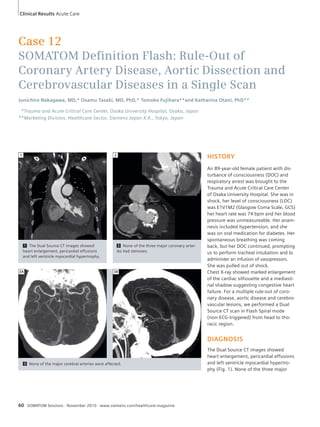

60 SOMATOM Definition Flash: Rule-Out

of Coronary Artery Disease, Aortic

Dissection and Cerebrovascular

Diseases in a Single Scan